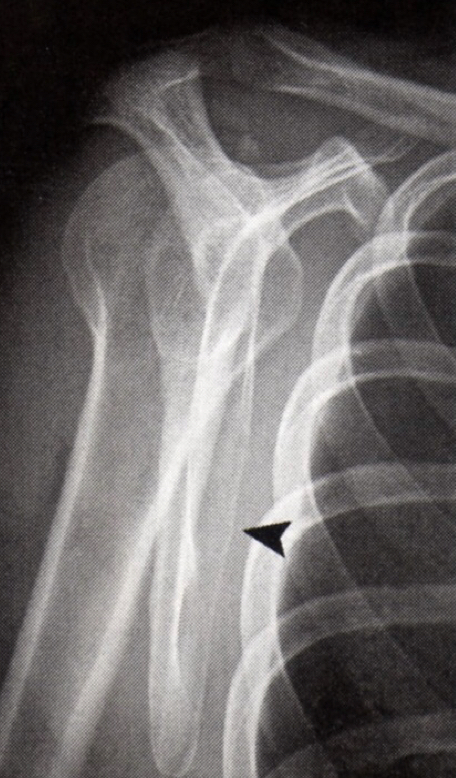

this deformity is due to repeated anterior dislocations (and on every baord exam ever per Lauri)

● Hill-Sachs Fx/Deformity

Hill-Sachs Fx/Deformity

Small fracture of glenoid rim that is frequently caused by reductions that don’t get enough clearing or dislocation

Bankart Fx

bankhart